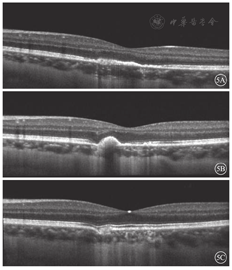

首诊后1周,左眼BCVA 0.3. OCT检查,黄斑区RPE增厚,反射增强,局部椭圆体带结构不清晰(图5A)。首诊后1个月,左眼BCVA 0.8。OCT检查,黄斑区RPE增厚,呈锥状隆起(图5B)。首诊后1年,左眼BCVA 1.0. OCT检查,外层视网膜结构清晰,RPE厚度接近正常(图5C)。眼底可见黄斑病变区呈盘状色素萎缩,中央有不规则色素沉着(图6)。

对于本病的诊断应根据病史结合眼底表现及影像学检查。本例患者为健康青年女性,双眼近视。有感冒发热病史,单眼视力突然急剧下降,黄斑区视网膜色素改变,FFA表现为透见荧光和遮蔽荧光,典型表现为病灶中心弱荧光,周边环形强荧光"牛眼"样外观[4]。OCT显示RPE及外层视网膜病变,早期RPE水肿,强反射物质堆积,椭圆体带中断、不连续。随着病程的发展,外层结构逐渐修复。OCTA可见脉络膜毛细血管层血流信号增强,未见异常新生血管。患者多模式影像学表现典型,根据以上临床特征AIM诊断明确。本病主要累及外层视网膜及RPE。观察本例患者整个病程OCT,推测急性期视力下降可能与黄斑区视网膜外层结构损伤有关。

本病为自限性疾病,有学者认为早期给予糖皮质激素治疗可抑制视网膜炎症反应,减少黄斑区损伤[5]。近年有学者报道本病可继发CNV,行抗VEGF药物治疗后视力恢复良好,但由于观察时间短,远期疗效并不明确[6]。本例患者因自身原因未接受任何治疗。经密切随访观察,发病后4~ 6周,RPE增生明显,外层视网膜结构逐渐恢复;视力预后良好,黄斑区出现色素性萎缩,1年内病情稳定,无复发。